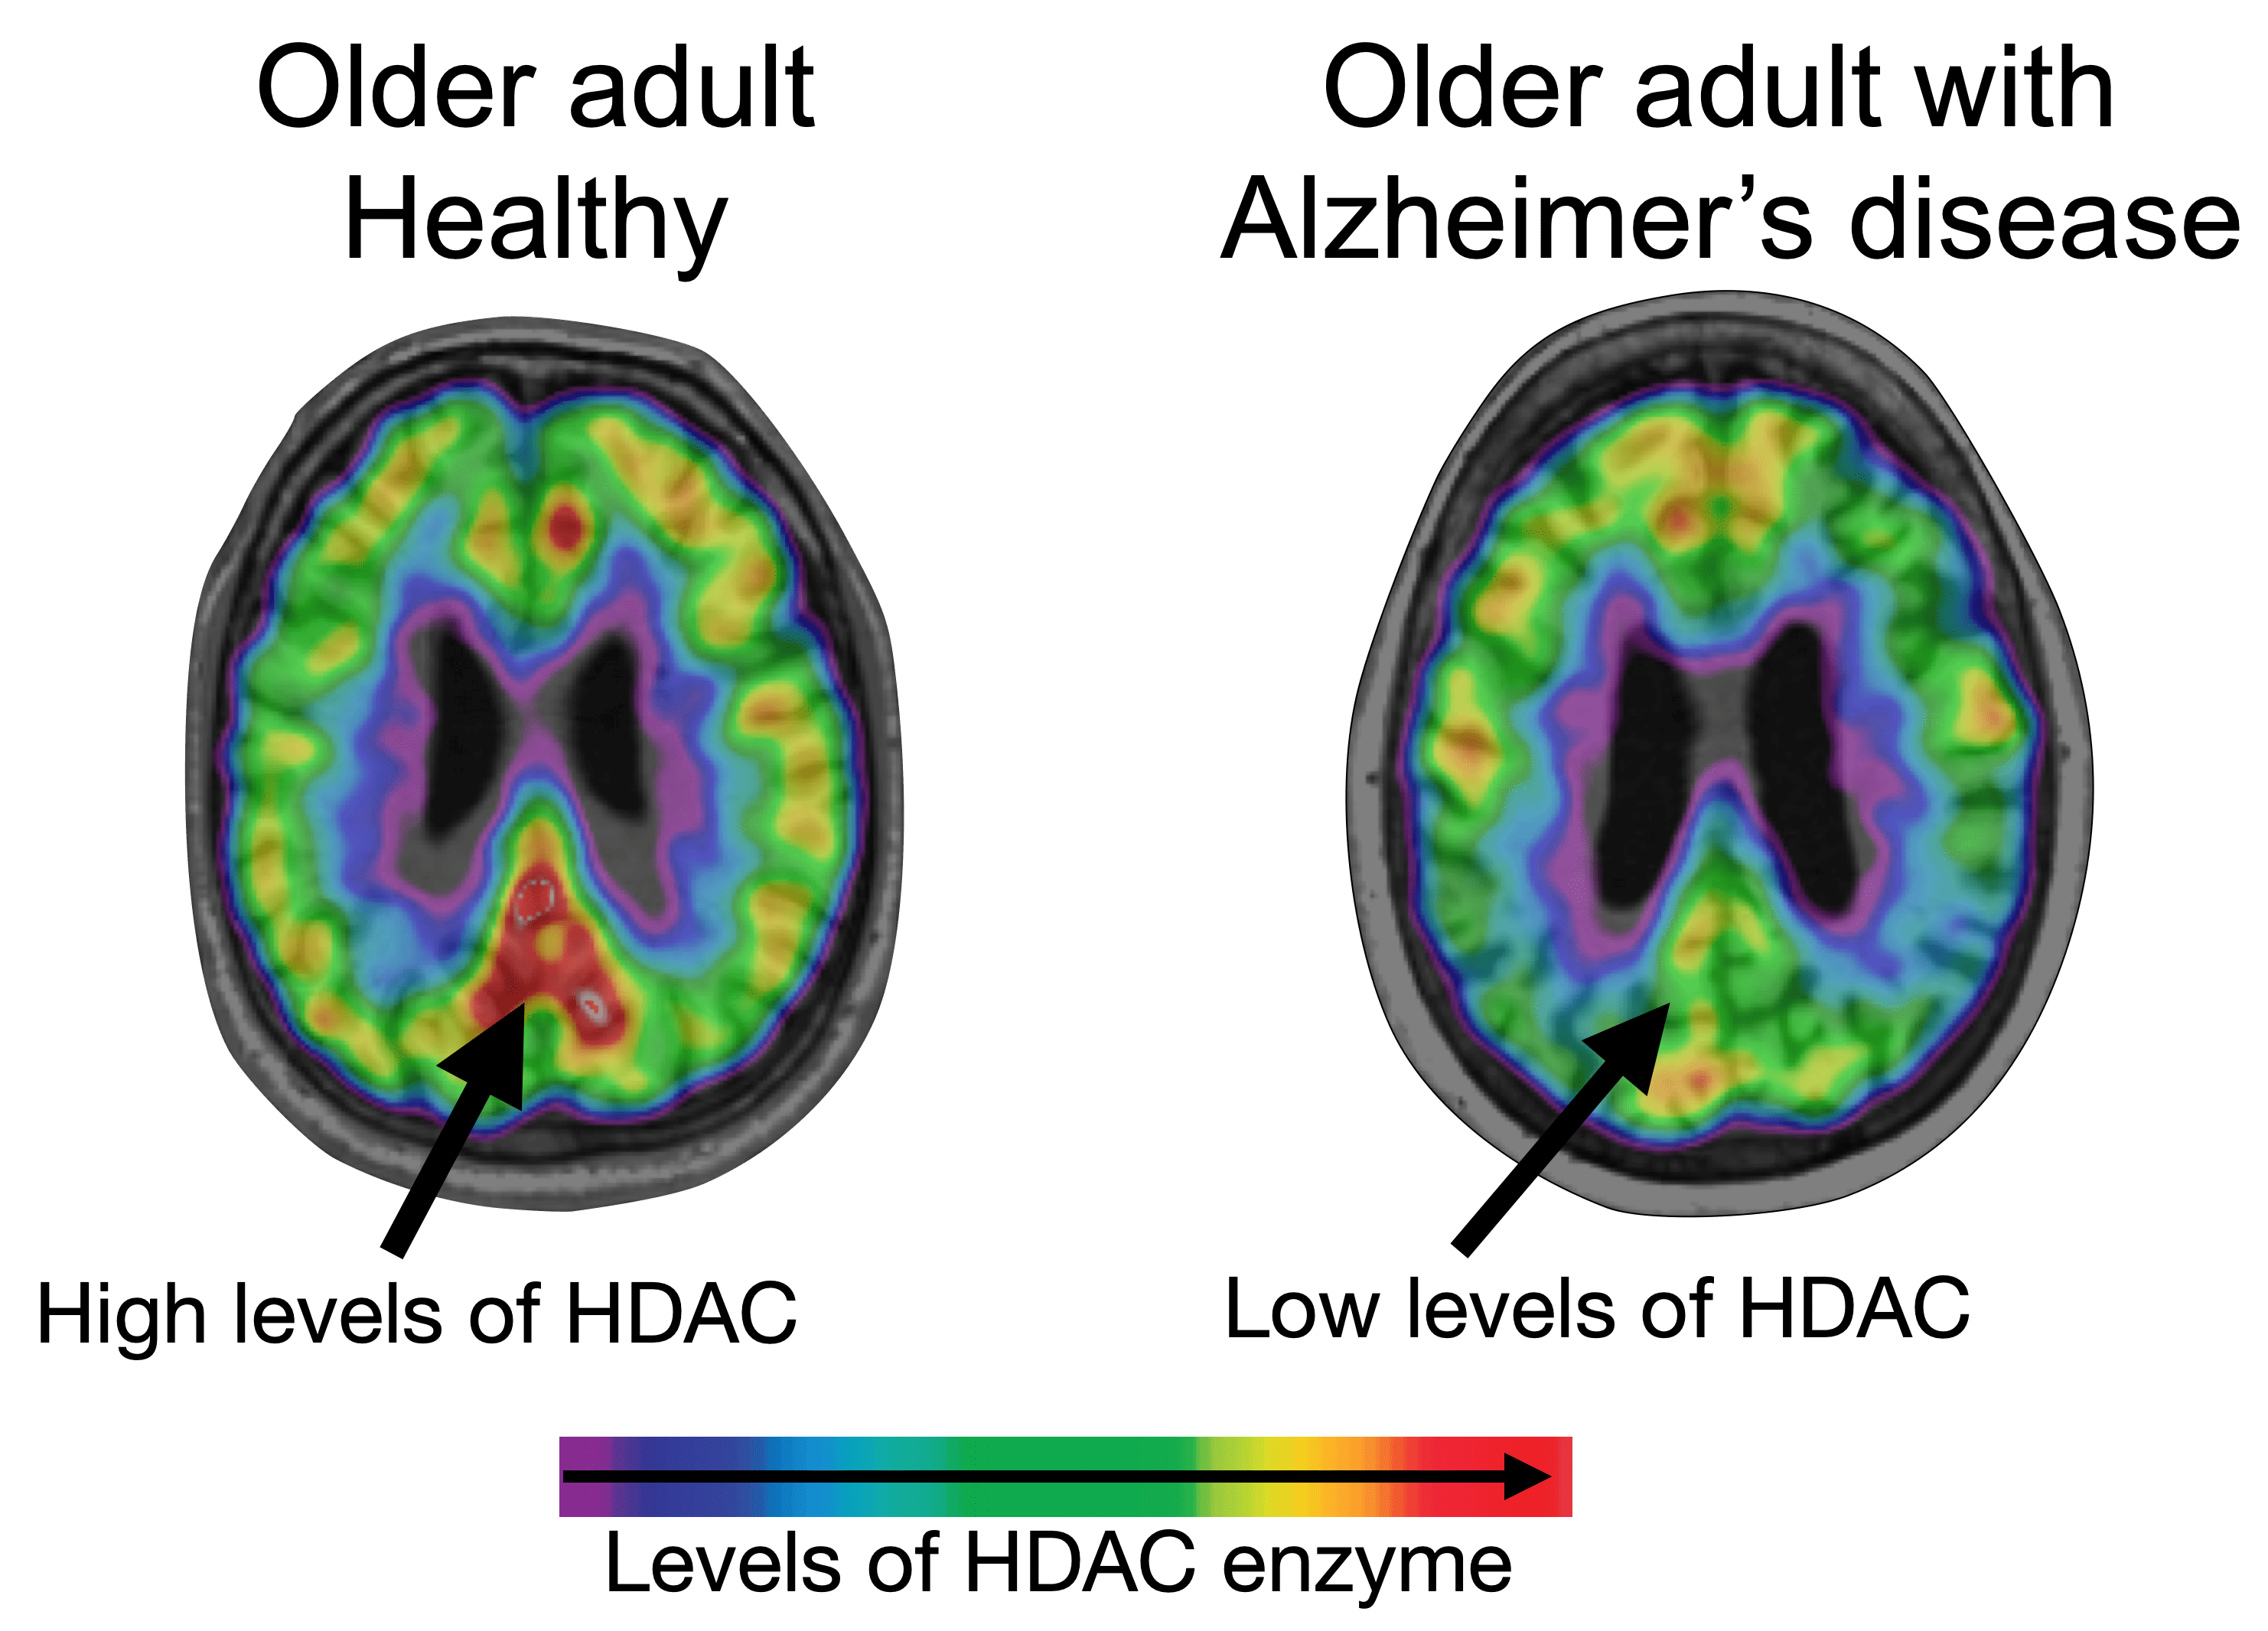

Using a selective molecular tracer called [11C]Martinostat, researchers showed that HDAC I levels were greatly reduced in the brains of people with Alzheimer’s disease compared to non-Alzheimer’s controls, specifically in regions buried deep inside the brain’s core – hippocampus and the midline -- as well as in the brain’s temporal cortex.

Analyses showed that reduced HDAC I in areas of the brain that are most susceptible to Alzheimer’s disease-associated degenerative changes corresponded to higher beta-amyloid and tau burden. It also predicted progressive neurodegeneration and cognitive decline over the two-year period.